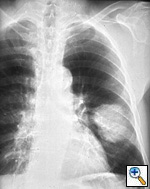

Fig. 8: Posterior-anterior radiograph shows a 6.5 cm left lower lobe bronchogenic carcinoma, T2, without hilar or mediastinal nodal metastases.